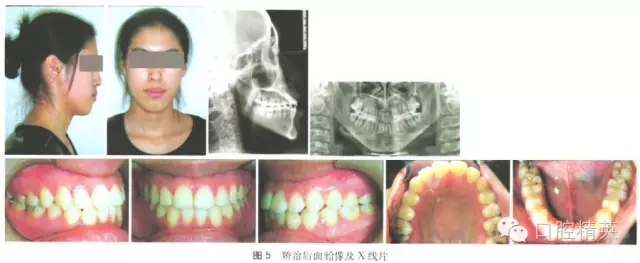

矯治后面型改善良好,直面型。雙側(cè)磨牙完全近中關(guān)系,前牙覆牙合覆蓋正常,上下牙排列整齊,上下中線居中、對齊,上下牙齒基本為尖窩鎖結(jié)關(guān)系。矯治結(jié)束后囑患者拔除四顆智齒。曲面斷層片顯示:牙根平行排列,未見明顯牙根吸收,治療前后頭影測量值見表1,治療前后頭影測量重疊圖見圖1,治療前中后面牙合像、X線片見圖2~5。